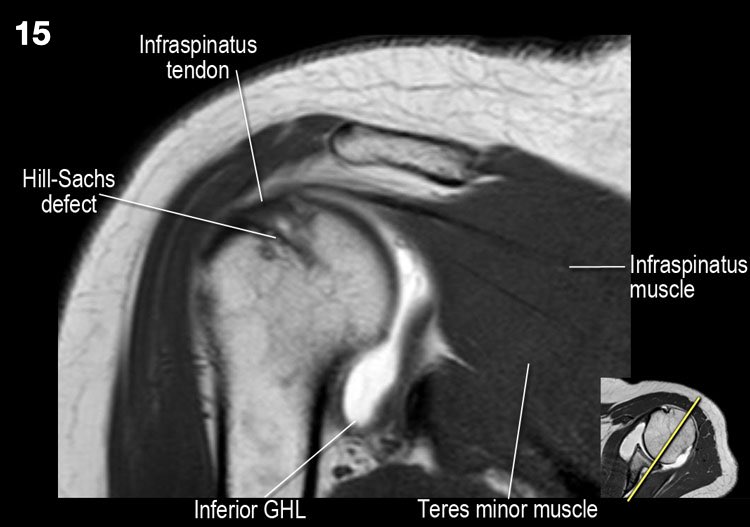

Ở mức này, cũng tìm kiếm tổn thương Hill-Sachs ở bờ sau-ngoài của chỏm xương cánh tay. - Các thớ sợi của gân cơ dưới vai giữ gân cơ nhị đầu trong rãnh của nó. Đánh giá sụn khớp.

Tổn thương Hill-Sachs chỉ được thấy ở mức mỏm quạ.

- Lưu ý tổn thương Hill-Sachs nhỏ.

Giải phẫu mặt cắt đứng dọc và danh sách kiểm tra

- Lưu ý các cơ chóp xoay và tìm kiếm dấu hiệu teo cơ.